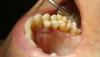

simpsons Опубликовано 5 ноября, 2012 Автор Поделиться Опубликовано 5 ноября, 2012 Видно старались, но я бы сделал имакс.На последней фотке очень хорошо видна схожесть ДЦ и МК. Оптические свойства хуже, чем у прессовки. Хотя, от техника многое зависит.Предпочтение к ДЦ было у пациента! Кстати пац из питера! У керам массы IPS In line вот такие оптические свойства как на моем фото.Может у кого-то другие результаты? Ссылка на комментарий

Bobby Опубликовано 5 ноября, 2012 Поделиться Опубликовано 5 ноября, 2012 Предпочтение к ДЦ было у пациента! Кстати пац из питера! У керам массы IPS In line вот такие оптические свойства как на моем фото.Может у кого-то другие результаты? Предпочтения должны быть у врача, а пациент либо соглашается, либо нет )Масса тут почти непричём. Акцент на каркасе и его маскировке. Работа хорошая. Служить будет. Вы молодец. Ссылка на комментарий

Юрьевич Опубликовано 7 ноября, 2012 Поделиться Опубликовано 7 ноября, 2012 Видно старались, но я бы сделал имакс.На последней фотке очень хорошо видна схожесть ДЦ и МК. Оптические свойства хуже, чем у прессовки. Хотя, от техника многое зависит.in line можно было сделать красивее,где тут ДЦ? Ссылка на комментарий

Юрьевич Опубликовано 7 ноября, 2012 Поделиться Опубликовано 7 ноября, 2012 Облицовка In.line! Какие отзывы о этой керамики? ДЦ не может быть облицован in line. Ссылка на комментарий